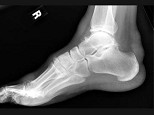

- 单项选择题男,47岁, 关节炎病史20年,结合图像, 最可能的诊断是 ( )

A、类风湿关节炎

B、痛风

C、骨关节结核

D、牛皮癣性关节炎

E、Reiter综合征